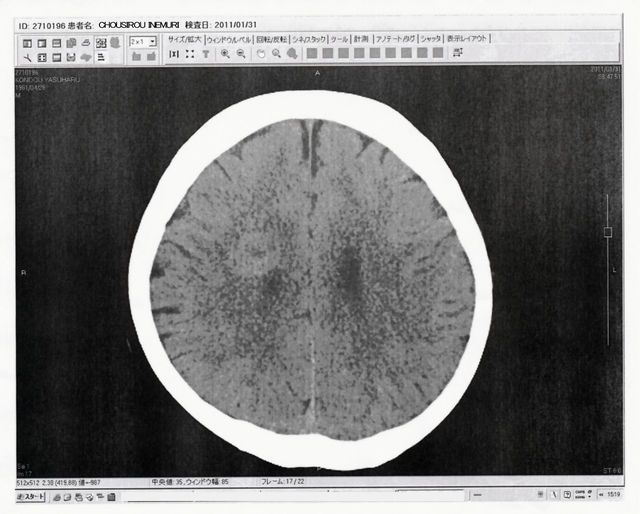

それと両肺10カ所の転移性再発病巣なんだが、これも抗ガン剤治療3クールにして、抗ガン剤治療開始前の半分サイズにまで縮小していた。見かけの直径が半分だから、縦横奥で計算すると、1/8になってるって事だよ。これまたビックリですよ。BEP療法がバッチリなんだよなぁ。そんでもって、たいした副作用が出ているワケでもないし、主治医のN尾先生からあらためて、「ここ2~3年のガン治療の進歩と、これから2~3年のガン治療の革新は凄まじいモノがありますよ。でも、その治療に耐える頑強な身、生命力を授けてくださったご両親に感謝してくださいね」と言われてしまった(笑)。いやいや、第一に先生に感謝させていただきます。N尾先生、M山先生、看護スタッフの皆さん全員が、本当に命の恩人です。心から感謝しています。